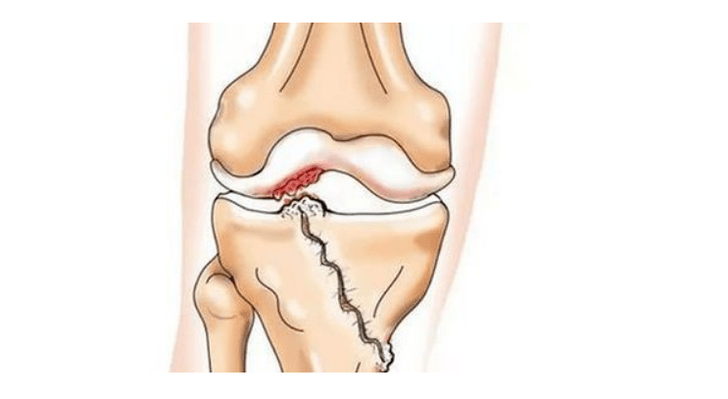

Antrinė kelio sąnario artrozė

- traumos (lūžiai, menisko ir priekinio kryžminio raiščio plyšimai). Deja, bet kuriam žmogui, nepriklausomai nuo amžiaus, šie sužalojimai sukelia pernelyg didelį kremzlės stresą. Bet kurios kremzle padengtos kaulų dalies lūžį lydi nelygumai - „žingsnis“. Šioje srityje judant atsiranda dilimas, formuojasi artrozė;

Sergant artroze (osteoartroze), be laipsniško kremzlės irimo, jos elastingumo ir amortizacinių savybių nykimo, į procesą palaipsniui įsitraukia kaulai. Esant apkrovai, atsiranda aštrių briaunų (egzostozės), kurios klaidingai laikomos „druskų nuosėdomis“ - esant klasikinei artrozei, druskos nenusėda. Progresuojant artrozei, ji toliau „valgo“ kremzlę. Tada kaulas deformuojasi, jame susidaro cistos, pažeidžiamos visos sąnario struktūros, sulinksta koja.